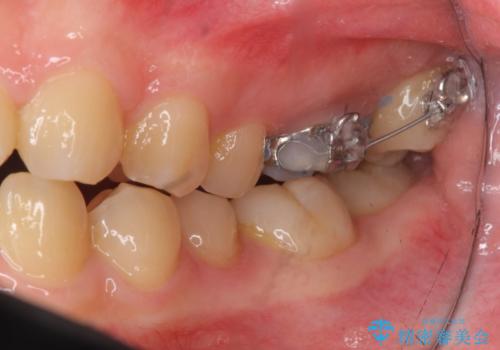

インビザライン治療は主に奥歯のかみ合わせが大きな問題がない場合は特に問題なく終了しますが、今回のケースのように奥歯のかみ合わせが悪い場合、しっかり治らないことがあります。

患者様が気づかない範囲で妥協して終わるということをせず、しっかり奥歯に部分矯正を用いて大きな問題を解決してからインビザライン治療に入りました。

奥歯のワイヤー部分矯正は位置的に人から気づかれることはないと思います。